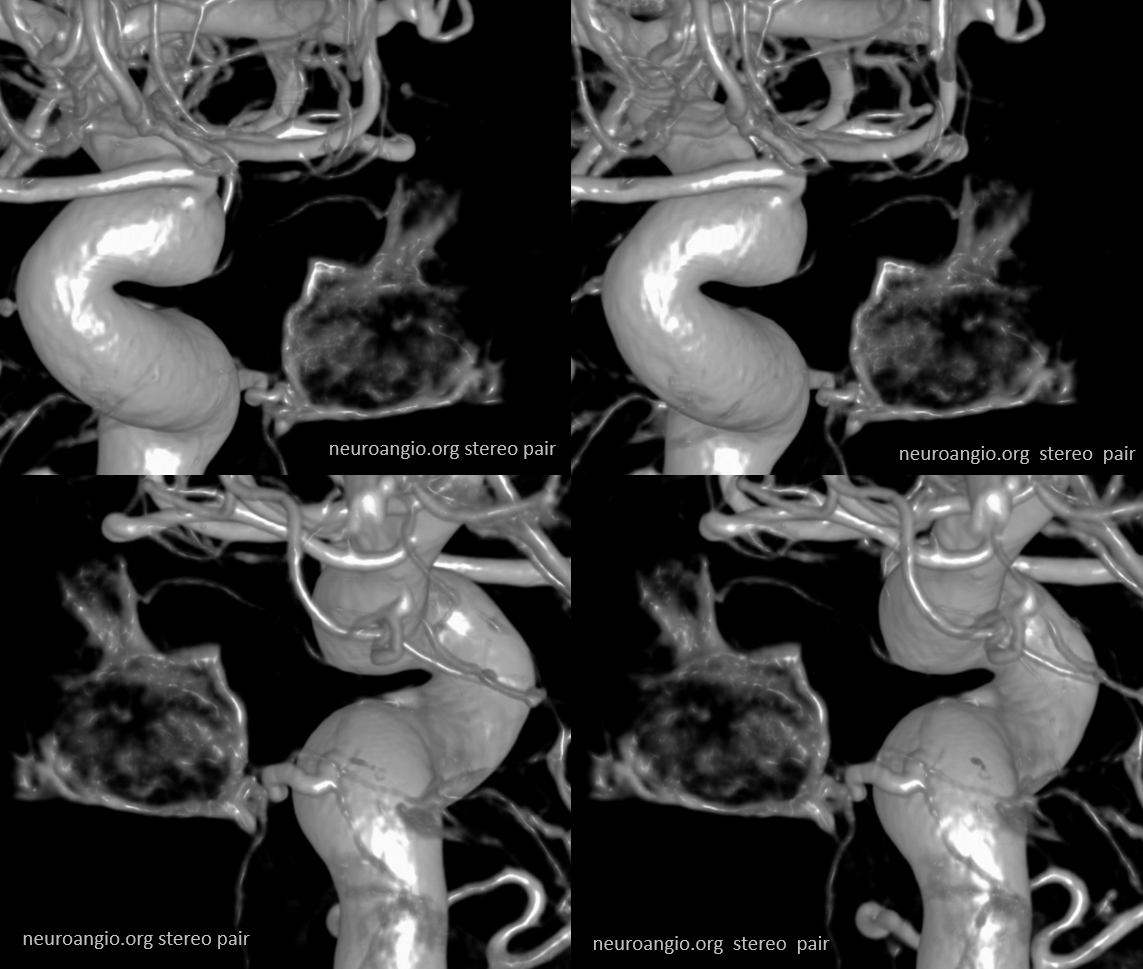

Stereos and MIPs. Both superior and inferior hypophyseals are well seen. The superior hypophyseal, despite being invisible on standard issue views, is quite large, even having two branches to the hypophysis.

Case courtesy Dr. Eytan Raz — here is a beautiful example of a very dominant superior hypophyseal artery (arrow) supplying the posterior hypophysis (arrowhead), with a correspondingly small inferior hypophyseal contribution from the MHT (dashed arrow)

Cross eye stereo

View from the back — again small inferior hypophyseal, big superior hypophyseal — balance again… See the beautiful vascular ring of the posterior pituitary — the connecting it with the contralateral side

Cross-eye stereo

MIP image shows the sella nicely — and helps prove its posterior pituitary

Pure arrowless images — easier to steal…

Of course, there is an aneurysm here — the branch point camp would point out how this larger than usual branch is a setup for aneurysmal formation. Naturally…